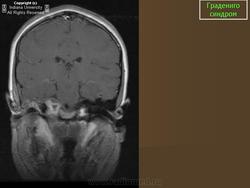

Градениго синдром.

(G. Gradenigo, 1859-1926, итал. оториноларинголог) сочетание симптомов гнойного воспаления среднего уха с парезом или параличом наружной прямой мышцы глаза, болями по ходу тройничного нерва, а также с тугоухостью, обусловленной поражением звукопроводящего и звуковоспринимающего аппаратов; возникает при ограниченном менингите в области верхушки пирамиды височной кости.